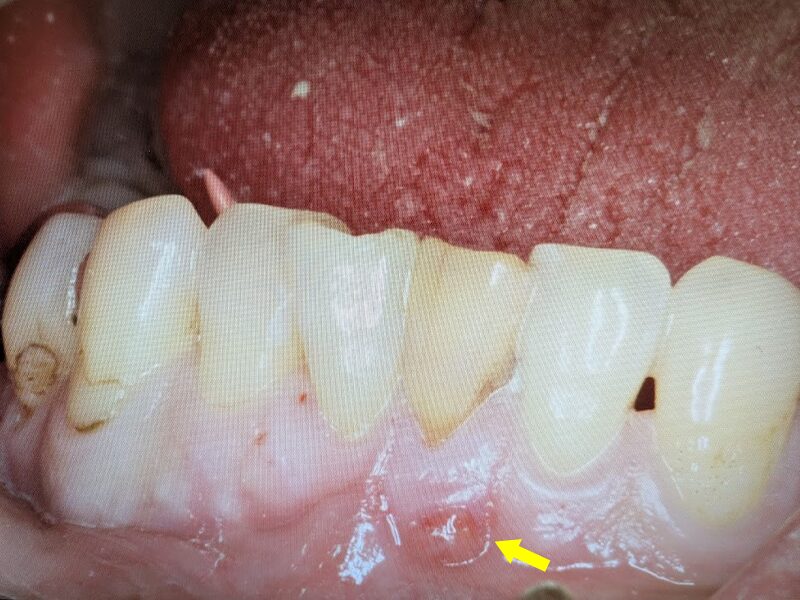

前歯1番の左下の歯肉に膿瘍が形成されておりました。患者様には状態を説明して根管治療から開始しました。

根管治療を行い、歯肉の膿瘍が消失しています。手術の準備が整いましたので手術を実施いたします。